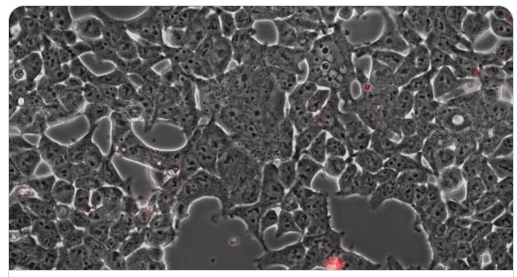

Après avoir infecté une cellule, le SARS-CoV-2 a (comme d’autres coronavirus) la capacité de faire fusionner celle-ci avec des cellules voisines aboutissant à la formation de structures nommées syncytia (des cellules géantes multinucléées)

Ici, la formation de syncytia par le SARS-CoV-2 dans des cellules nerveuses de chauve-souris

A microscopic video shows the coronavirus on the rampage.Inside a bat’s brain, the pathogen destroys cells, but not before it forces them to build more invaders.https://www.nytimes.com/2021/08/22/science/microscopic-bat-brain-virus.html

Il est évident que la formation de cellules géantes n’est pas naturelle dans le tissu et fait partie des mécanismes pathogènes du SARS-CoV-2 …

Ici des syncytia visibles dans les pneumocytes de personnes décédées du COVID

Il a été démontré que cet effet cytopathogène pouvait être reproduit uniquement avec la spike (sans le virus) puisque des cellules transfectées qui n’expriment que la spike sont capables de reproduire cet effet « syncytia inducer »

Cette belle vidéo montre la fusion cellulaire en temps réel aboutissant à la formation des syncytia. La cellule verte exprime la spike à sa surface et la cellule violette exprime ACE2

La formation des syncytia est due à l’interaction entre

-la Spike exprimée à la surface de la cellule infectée et

-le récepteur ACE2/TMPRSS2 exprimé à la surface des cellules non-infectées

Cette propriété à produire des syncytia est reconnue comme jouant un rôle dans la virulence.